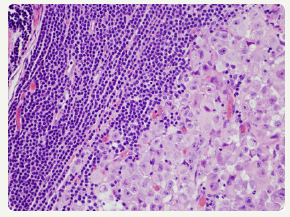

The occurrence of two dissimilar categories of malignant lymphoma arising within an individual in a sequential manner or as a simultaneous event incriminating the aforementioned lymph node groups may be infrequently elucidated. The emergence of two distinct and well described categories of lymphoma appearing within a singular anatomic site or nodule may be designated as composite lymphoma [2,3]. The association of two divergent subtypes of lymphoma at concurrently emerging at several anatomic sites may be classified as discordant lymphoma (Figure 2). The concordant lymphomas may signify the appearance of two contradistinctive neoplasm either spontaneously or as a consequence of therapeutic intervention of a preceding malignancy. Majority of composite/ discordant lymphoma may signify the emergence of discrepant biologic and morphologic elucidation of the same lesion where the aggressive variant represents the histological manifestation of tumour progression. Composite lymphomas as an exceptional entity may account for an estimated 1%-4% of the de novo malignant lymphomas.

Figure 2:CL: peripheral T cell lymphoma and a small lymphocytic lymphoma [14].